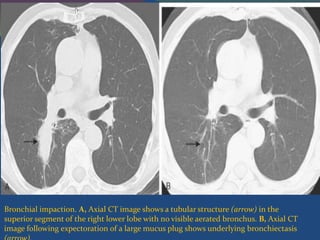

Bronchial impaction. A, Axial CT image shows a tubular structure (arrow) in the

superior segment of the right lower lobe with no visible aerated bronchus. B, Axial CT

image following expectoration of a large mucus plug shows underlying bronchiectasis